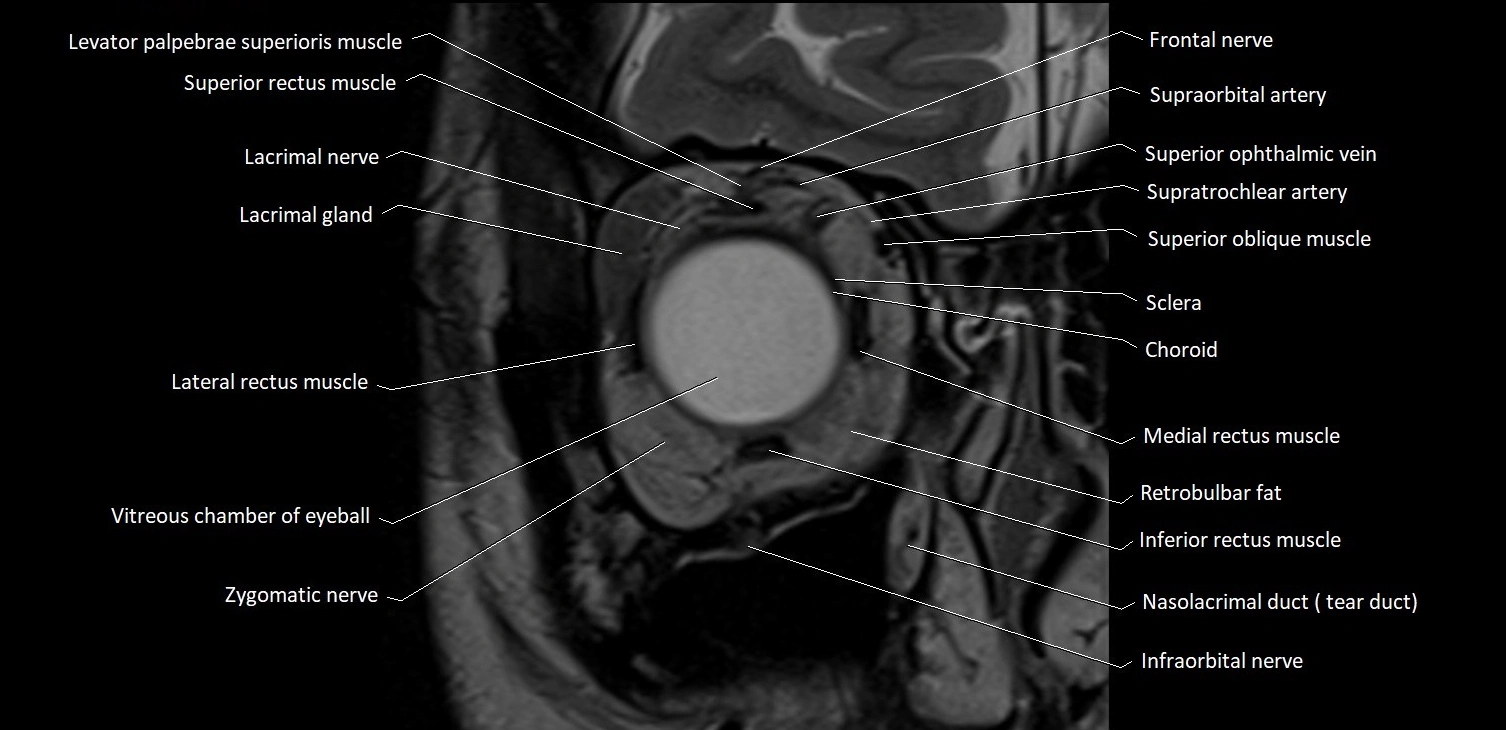

- Abducens nerve (Cranial nerve VI)

- Abducens nerve (orbital part )

- Lateral rectus muscle

- Inferior rectus muscle

- Medial rectus muscle

- Superior oblique muscle

- Superior rectus muscle

- Retrobulbar fat

- Infraorbital nerve

- Zygomatic nerve

- Lacrimal gland

- Lacrimal nerve

- Superior ophthalmic vein

- Supratrochlear artery

- Supraorbital artery

- Frontal nerve

- Vitreous chamber of eyeball

- Sclera

- Choroid

- Nasolacrimal duct (Tear duct)